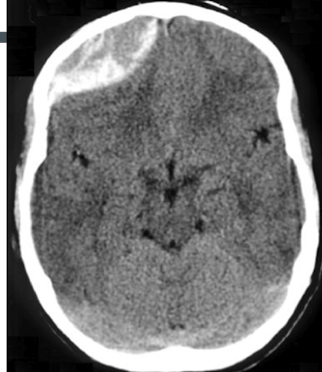

Q

Where is the blood

A

intraventricular